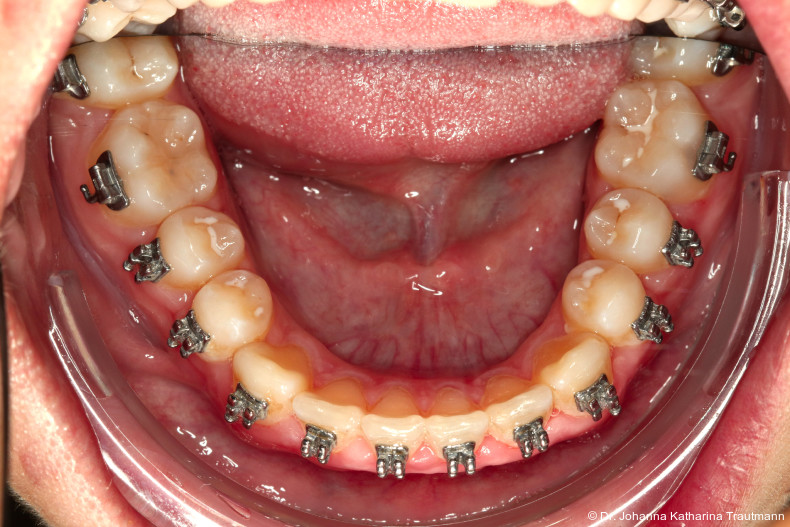

Nach etwa zwei Jahren initialer Behandlung konnte nach abgeschlossenem Wurzelwachstum aller bleibenden Zähne (mit Ausnahme der Weisheitszähne) mit der Hauptbehandlung unter Verwendung einer vollständigen Multibracketapparatur von 7 bis 7 im Ober und Unterkiefer begonnen werden. Die vergleichsweise lange Vorbehandlung erscheint zwar auf den ersten Blick behandlungszeitverlängernd, sorgt jedoch für eine deutlich bessere Mundhygienefähigkeit sowie für eine Reduktion des apparativen Aufwandes und der biomechanischen Komplexität in der Hauptbehandlungsphase. Diese Faktoren stehen in engem Zusammenhang mit Patientenkomfort und Motivation.

Studien zeigen, dass insbesondere Schmerzsensationen und Unbehagen in den ersten Tagen einer kompletten festsitzenden Apparatur erheblichen Einfluss auf die langfristige Kooperationsbereitschaft haben können.11, 12 Kleinere Teilapparaturen verursachen weniger Diskomfort und erleichtern so den Einstieg in die festsitzende Therapie.

Im Rahmen der Multibrackettherapie wurde bewusst der Zahn 13 aus dem Hauptnivellie rungsbogen ausgelassen, um Kippungen und Asymmetrien im Zahnbogen zu vermeiden. Der Zahn 23 wurde locker mit einer Distanz ligatur angebunden, um eine weitere Bewegung nach vestibulär zu erreichen. Auf einem 0.019" x 0.025" Stahlbogen erfolgte anschlie ßend mittels Umgehungsbiegung sowie eines Overlaybogens (0.014" NiTi) die Integration des Zahnes 13 in den Zahnbogen. Die Zwischendiagnostik nach einem Jahr festsitzender Behandlung zeigte eine gelungene Bisshebung bei guter Nivellierung des Okklusionsplanums und orthoaxialer Einstellung der Frontzähne. Die Zahnbögen präsentierten sich harmonisch ausgeformt, es zeigte sich jedoch eine verbleibende Torqueproblematik an bei den Oberkiefereckzähnen. Nach Freilegung und Einstellung verlagerter Eckzähne ist eine korrekte Torque und Angulationssteuerung häufig eine Herausforderung. Während vestibulär verlagerte Zähne zu gingivalen Rezessionen neigen, behalten palatinal verlagerte Zähne oft ihre palatinale Wurzelstellung bei.13, 14 Die genutzte MBTPrescription der Brackets bietet die Möglichkeit, zwischen +7°, 0° und –7° Torque zu wählen.15 In einem 0.022" System ist bei Verwendung eines 0.019" x 0.025" Bogens jedoch mit einem Torqueverlust von etwa 10° zu rechnen.16